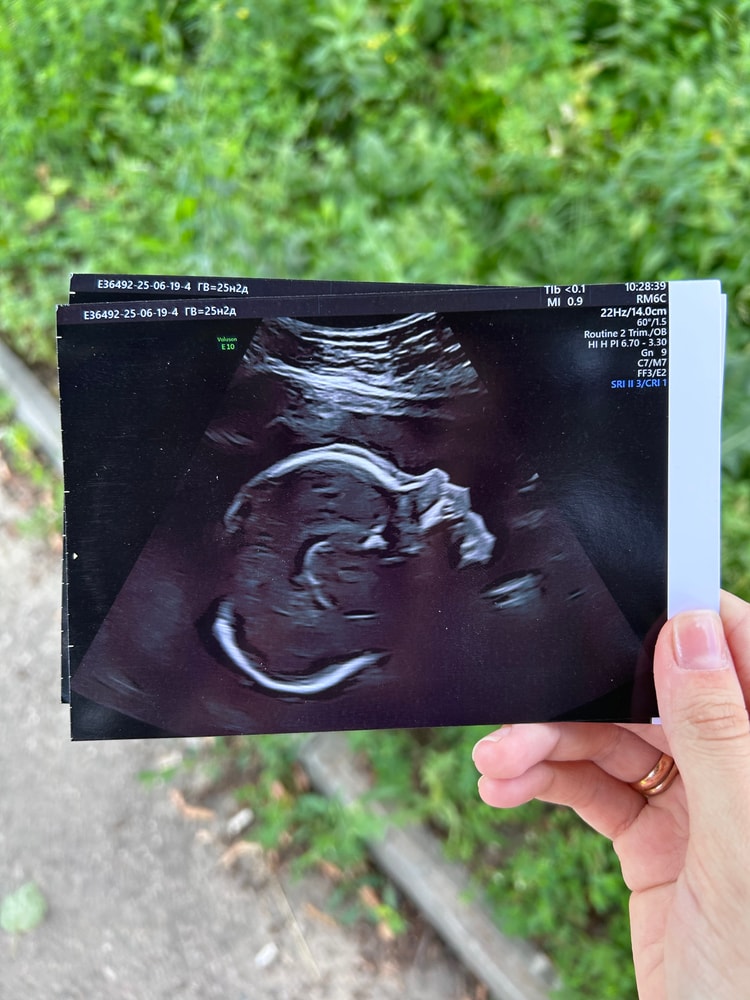

Очень красивый 😍

У моего на УЗИ тоже был такой носик, собственно, и родился с таким, очаровательный нос, очень красивый. Я сказала - слава богу, что не как у меня🙈

У меня на таком узи- фото был похож на Караченцева, родился- не похож.

Если вы мечтали о римском ли греческом профиле у ребенка, то к сожалению, такому не бывать)) Он будет похож на вас или вашу родню.

Обычно такие детские головушки бывают на вышивках. Какая милота!

Нормальный, он может и не курносый вообще. Дочка родилась с приподнятым носом-пуговкой, сейчас 2 года и совершенно другой

У нас такой был😁

Спасибо что не мой нос, а мужа 😅